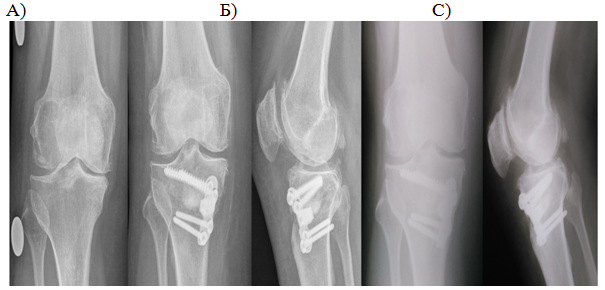

When studying the radiographs in the direct and lateral projections, disclosure of the joint gap was noted 3 months after the operation. Progression of medial compartment OA after a year did not occur, degenerative changes in another compartments were also absent (Figure 2) (Figure 3).

Figure 2 Patient T., 57 years old, 3-rd stage OA of the right knee. Before surgery (A), after 3 months (B), and 1 year (C) after surgery.